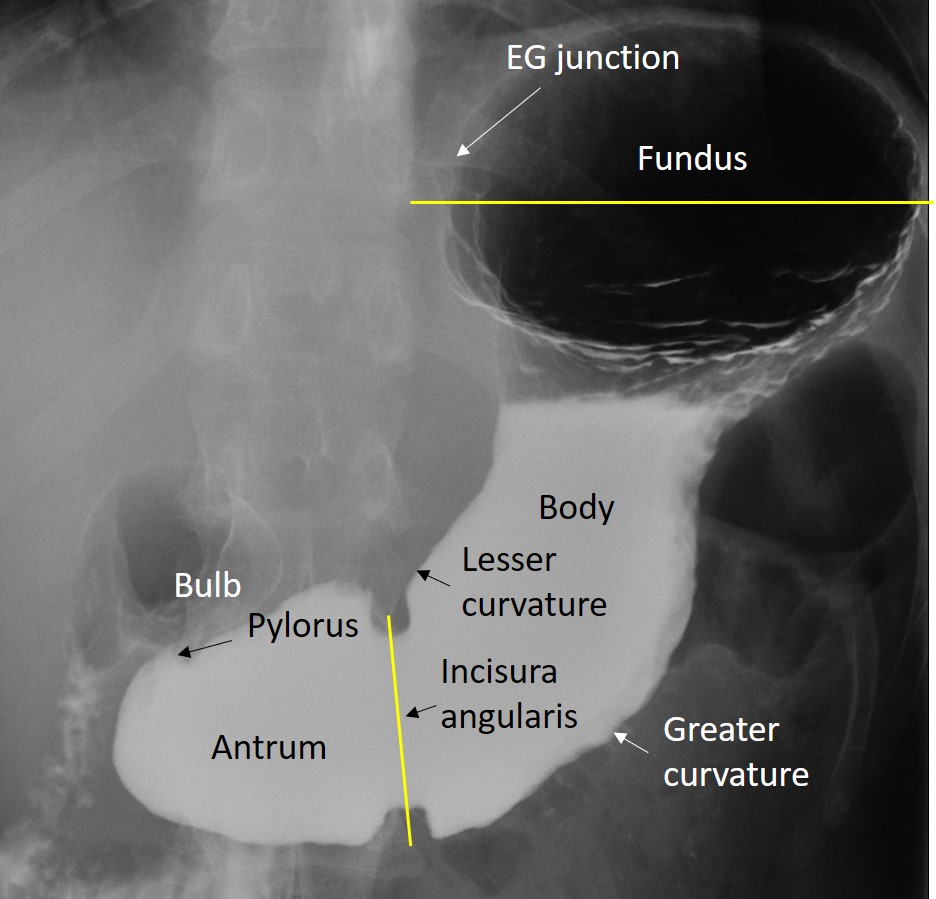

Gastric cardia radiology. Diagnostic centers of america dca is a leading diagnostic imaging facility offering a full array of imaging services in palm beach county florida. We have five state of the art radiology imaging centers in boca raton boynton beach delray beach and wellington florida. The gastric cardia is characterized on barium stud ies by three or four stellate folds that radiate to a central point at the gastro esophageal junction also known as the cardiac rosette fig 2 12. Variations and benign influences may closely resemble the more dangerous lesion.

Cain jc jordan gl jr comfort mw gray hk. J am med assoc. The gas tric fundus is dened as the portion of the stomach craniad to the gastric car dia. Commonly accompanying this are abnormally dilated short gastric veins which pass from the splenic vein to encircle the gastric fundus and form gastric fundal varices.